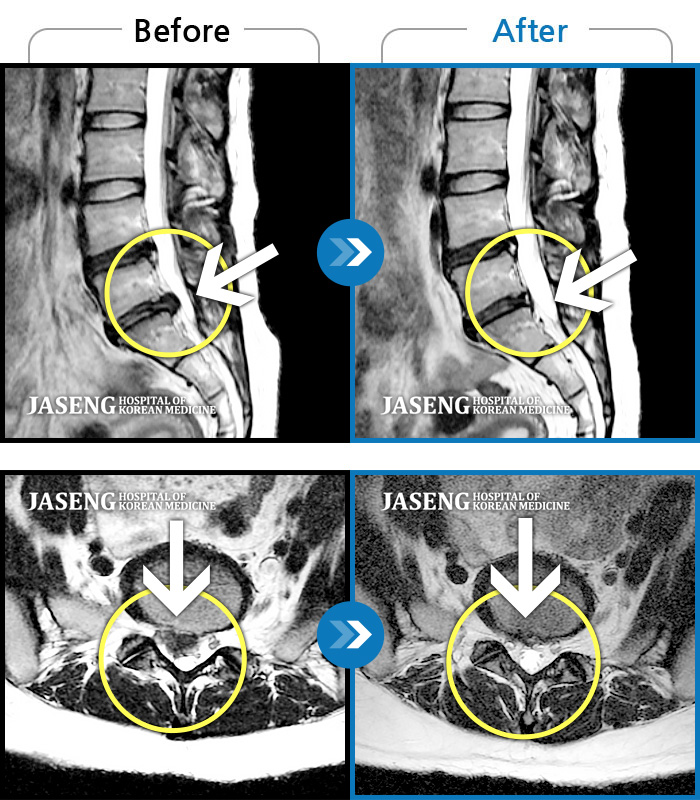

Before

After

환자에게 사전 동의를 받아 동일 조건에서 촬영되었습니다.

개인에 따라 치료 후 부작용이 발생할 수 있으니 의료진과 상담 후 치료를 진행하시기 바랍니다.

허리 양측 골반에서 우측 허벅지 외측으로 통증, 5분 정도 기립 시 당기고 저리는 증상

허리통증, 왼쪽 다리 저림 및 통증